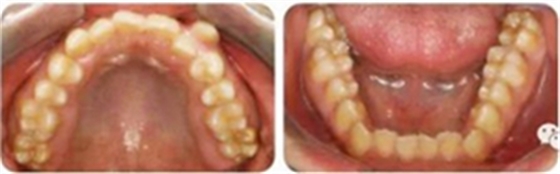

影像學(xué)檢查

無缺牙及多生牙,雙側(cè)下頜升支高度相等,智齒未萌。

頭影測(cè)量顯示為骨性Ⅲ類高角患者。